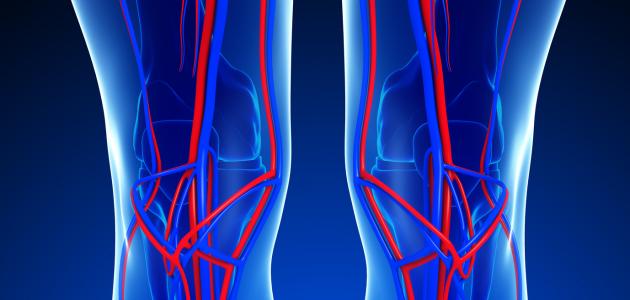

يحتاج الجسم لمادةٍ ناقلة تكون حلقة وصل بين المواد المُراد نقلها والأعضاء والخلايا المختلفة؛ حيث يؤدّي هذه الوظيفة المهمة الجهاز الدوراني في جسم الإنسان وهي شبكة واسعة من الأعضاء والأوعية الدموية، وهي مسؤولة عن تدفق الدم في جميع أجزاء الجِسم.

يُعتبر سريان الدم في أنسجة جسم الإنسان ذا أهميّةٍ كبيرةٍ لبَقاء جَميع الأعضاء حيّة، حيث أنها تنقل الأكسجين والهرمونات والغذاء والغازات الأخرى من وإلى الخلايا، ومن دون هذا الجهاز فإنّ الجسم يكون غير قادرٍ على مُحاربة الأمراض أو الحفاظ على استقرار الحرارة والحموضة والبيئة الداخلية للجسم.[٢]

تنقسم الدورة الدموية في الجسم إلى دورة دموية صغرى ودورة دموية كبرى وكان لاكتشاف آليّة عمل الدورة الدموية الثورة في مجال الطب؛ فكثيرٌ من الظواهر في جسم الإنسان تمّ تفسيرها بناءً على هذا الشرح.

تدور الدورة الدمويّة الصغرى بين الرئتين والقلب؛ حيث يَنقسم القلبُ إلى بُطين أيمن وبطين أيسر، وأذين أيمن وأذين أيسر، وتحمل الأوعية الدمويّة (الشريان الرئوي) الدم الذي يحتوي على ثاني أكسيد الكربون والسموم من البُطين الأيمن في القلب إلى الرّئتين لاستبدالها بدم يحتوي على الأكسجين والغذاء عن طريق تحرير ثاني أكسيد الكربون واتّحاد كُريات الدم الحمراء مع جزيئات الأكسجين من الرئتين، ثمّ تعود به الأوردة الرئوية إلى الأذين الأيسر في القلب مرّةً أخرى ليُوزّعه على باقي أجزاء الجسم من خلال الدورة الدموية الكبرى.[٥]

تدور الدورة الدموية الكبرى بين القلب وأجزاء الجسم المختلفة باستثناء الرئتين؛ حيث ينقل الشريان الأبهر الدم المليء بالأكسجين إلى الشرايين والشُعيرات الدموية التي تنتشر في جميع أجزاء الجسم لتوصيل الأكسجين إلى الخلايا من أجل إتمام عملية التنفس الخلوي داخل الميتوكندريا، وفي الوقت نفسه يتم امتصاص ثاني أكسيد الكربون عبر الأوردة الصغيرة التي تنقل هذا الدم المُلوّث بثاني أكسيد الكربون إلى الأوردة الدموية الأكبر ثم إلى الوريد الأجوف الأعلى والوريد الأجوف الأسفل ثمّ إلى قسم القلب الأيمن، الذي بدوره يبدأ الدورة الدموية الصغرى التي تستبدل الدم الذي يَحمل ثاني أكسيد الكربون بدمٍ يحمل الأكسجين.[٥]

يحتوي جهاز الدوران على أجزاء مهمة تُعتَبر من أهمّ الأجزاء الوظيفية في جسم الإنسان، وهي:[٥]

- الشرايين.

- الأوردة.

- الشعيرات الدموية.